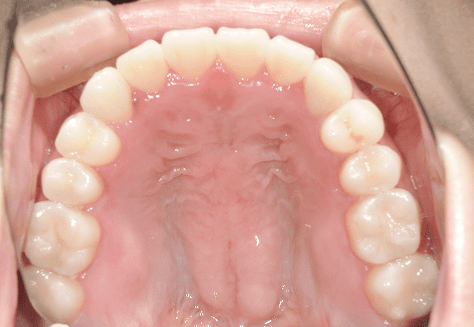

M.H

治療前

治療後

主訴

前歯が出ている。下の歯並びが特に気になる。奥歯でしっかり噛めない。

診断

上顎前突・叢生・シザーズバイト

年齢/性別

20代/男性

抜歯部位

下顎両側大三大臼歯(口腔外科にて)

上顎両側第一小臼歯・下顎左側側切歯

(当院にて5,500円×3) -

使用装置

上下エッジワイズ→インビザライン(PBM使用)

保定装置

上下ビベラリテーナー

料金

初回資料採得・・・・・・・30,000円

診断料・・・・・・・・・・33,000円

動的治療終了時資料採得・・5,500円 -

基本料金

880,000円

診察料金

5,500円×44回

治療期間

3年6カ月